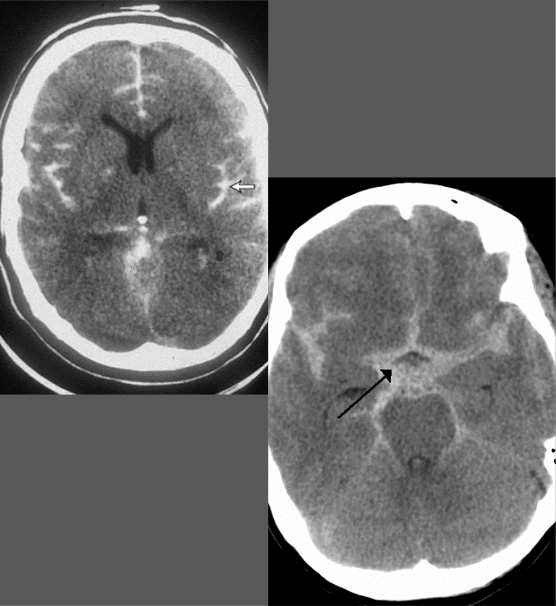

What is this pathology?

Subarachnoid Hemmorhage